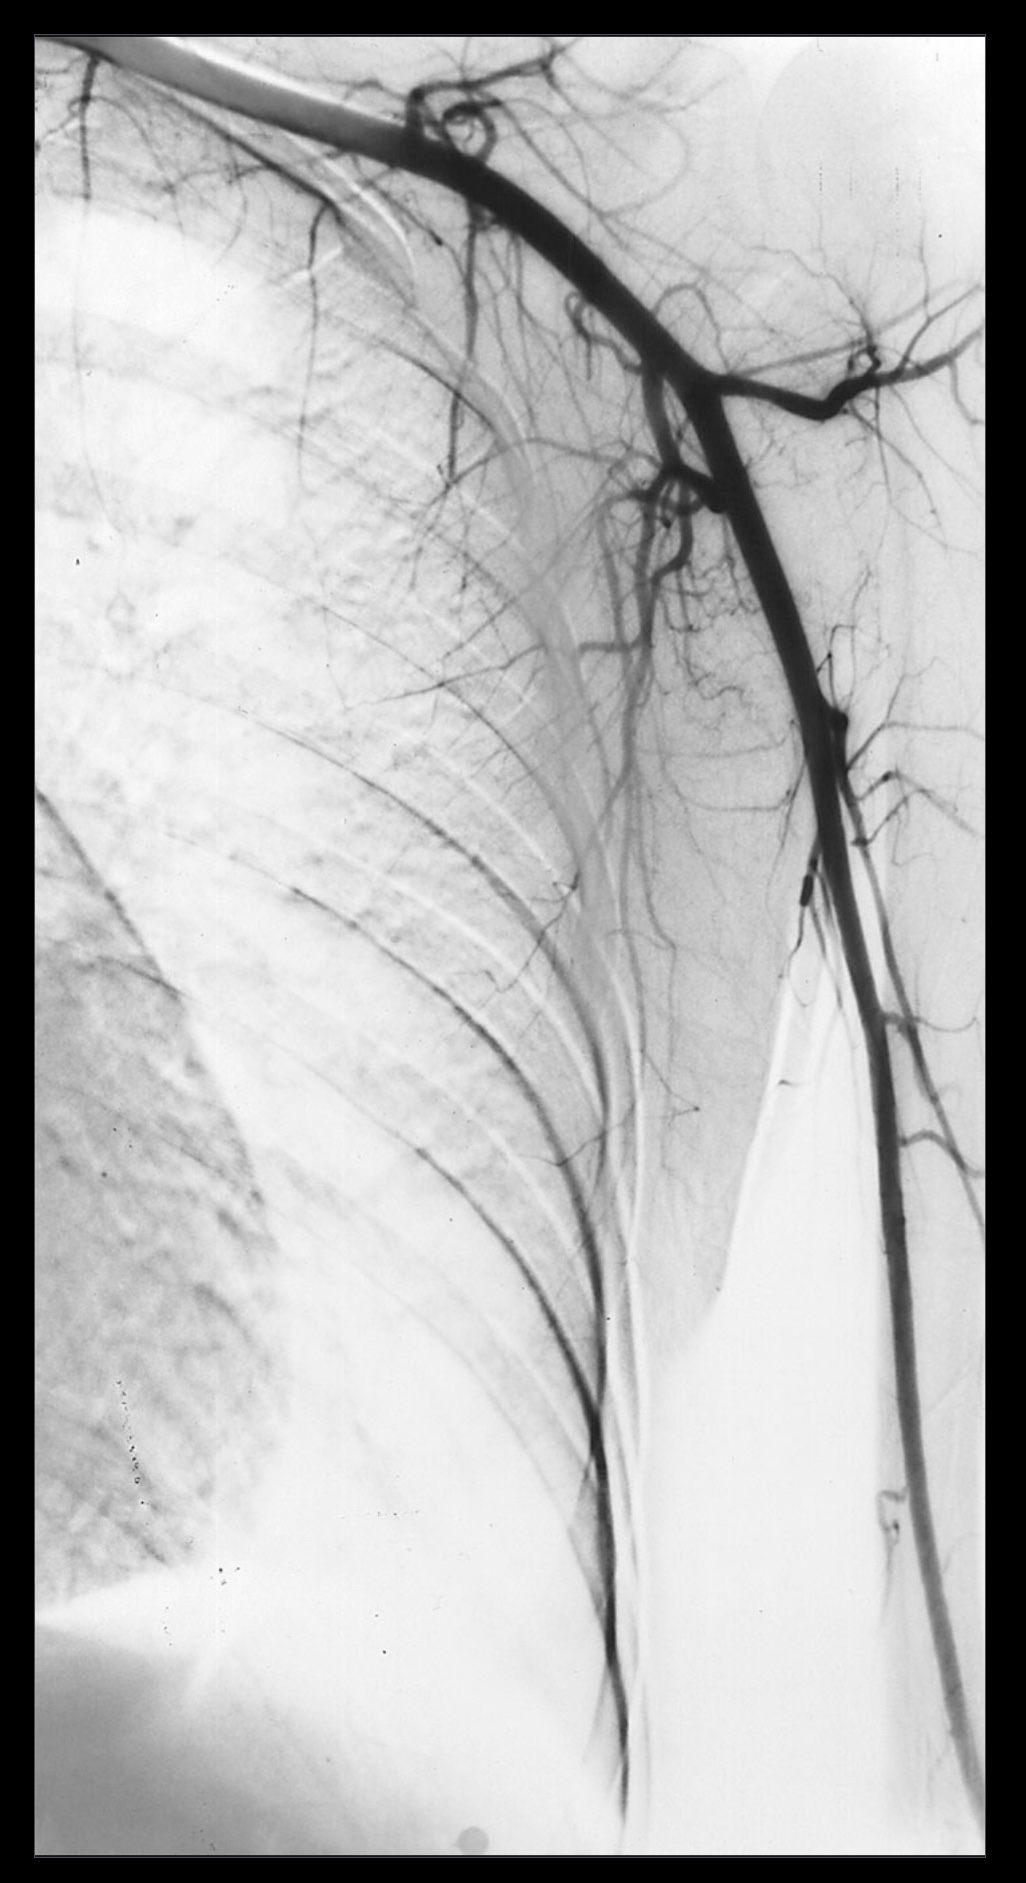

1. A patient complains of shoulder pain and difficulty rotating their arm. An ultrasound reveals edema within the spinoglenoid notch, which could explain weakness in external rotation at the glenohumeral joint. Describe the normal scapular and shoulder anastomosis, including all arterial branches involved and their relationship to any ligaments, scapula borders, and intermuscular spaces. If the axillary a. is ligated immediately distal to the thyrocervical trunk, would this edema affect active collateral circulation? (If yes, explain.) Also, include a brief (2-3 sentences) explanation for why edema within the spinoglenoid notch might result in weak external/lateral rotation of the shoulder.

4. The shoulder anastomosis provides adequate blood supply to the upper extremity during acute ligation of the axillary artery proximal to the subscapular artery. (False)

5. The scapular anastomosis provides adequate blood supply to the upper extremity during acute ligation of the axillary artery proximal to the subscapular artery. (True)

7. Acute axillary artery ligation proximal to the subscapular artery causes retrograde blood flow in the circumflex scapular artery. (True)